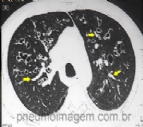

Mesa redonda no CHEST 2015 revisou o diagnóstico e o tratamento das principais formas de aspergiloses pulmonares. Resumimos as principais informações referentes à Aspergilose Broncopulmonar Alérgica e à Aspergilose Invasiva. ASPERGILOSE ...